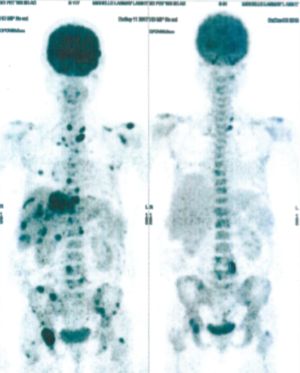

CASE NO: 3 (PROSTATE CANCER)

A middle-aged man with castration resistant prostate cancer, having failed all currently available cancer treatment, was very weak, and getting worse every day. The PET/CT scan showed he had massive bone metastases. After a few treatment, all the bone metastases went into remission. About 6 months later, he is still in remission.

CASE NO: 4 (PROSTATE CANCER)

A middle-aged man with castration resistant prostate cancer and massive bone metastases, failed all currently available cancer treatment, including with the new and expensive drug XTANDI. After a few treatment, most of the bone metastases went into remission, and the remaining ones are less active. Treatment will continue. Cases no: 3 and 4 show that terminal prostate cancer today can be cured with our new cancer treatment.